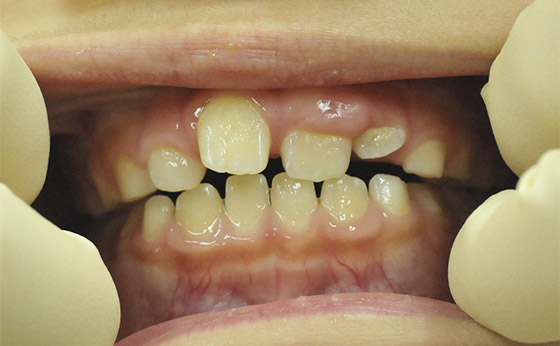

途中経過02

4か月でここまで改善しましたが、左の前歯だけが反対に噛んでます。